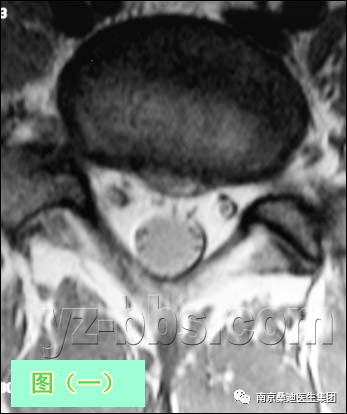

图(一)及图(二)是L5椎间盘的轴状面观。 此病人虽有中等程度的腰椎间盘退变(在片子上看到黑色的椎间盘)和小的非压迫性4mm的中央型椎间盘突出,但他却有一个很大的“中央管”,可以很好地表现轴向核磁共振解剖。椎间盘的髓核在这两个图像中看不到,一是因为椎间盘脱水太严重,不能将纤维环及髓核区分开,另外这些图像为T1加权象(更高分辨率),所以不能将含水多的髓核与较干燥的纤维环区分开。但在一个正常的,非退化性椎间盘T2加权像上,很容易看清髓核区及纤椎环区T2加权图像(见图三)。 “后部神经结构”包括过往神经根(Traversing Nerve Roots)、硬膜囊(Thecal Sac)及发出神经根(Exiting Nerve Roots)。发出神经根位于椎间孔(看图中IVF粉红色区)内,在此图像中看不到。如果你发挥点想象力,你可以在图中找到一个象“米老鼠”样的图像,硬膜囊是米老鼠的头,两个过往神经根是米老鼠的耳朵。再重复以下,虽然此椎间盘有4mm的突出,但此病人的过往神经根S1和突出物之间没有接触。 大部分情况下,椎间盘突出物或疤痕组织将遮挡住其中的一个过往神经根(米老鼠耳朵),这通常是神经根受压的象征。